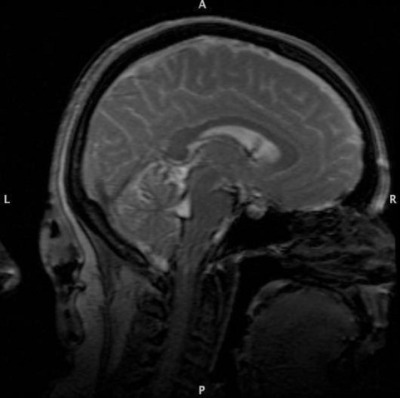

I came across these during a harddrive cleanup. I haven't seen these in a while. Ladies and gentlebeings, my brain. Sometimes I wonder if I should be saddened by the disturbing amount of symmetry, or relieved.

I got them as part of a psych study I volunteered for many years ago.

Brain MRI Brain MRI